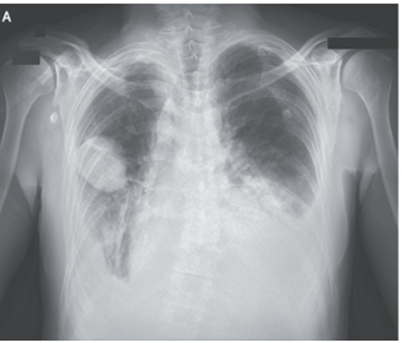

5日間連続する呼吸困難感を主訴に50歳男性が救急外来を受診した。

受診時身体所見では、頚静脈の拡張と肺基部の呼吸音の減少、心尖部での全収縮期雑音を聴取した。

胸部Xp施行。不明瞭な肺血管分布、心拡大、CPA dull所見を認めた。また右中肺野には境界のはっきりしたレンズ状病変を認めた。

心エコーではEF 45%、重度の僧帽弁逆流を認めた。

僧帽弁逆流に伴う心不全と診断し、利尿薬と血管拡張薬投与がなされた。3日後のX-p所見。